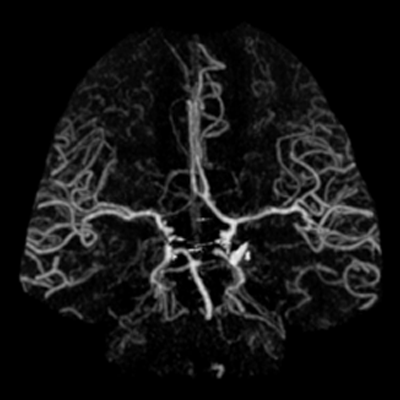

You arrive at the patient's room. You quickly examine her. Her left pupil is truly dilated and unreactive. Her right pupil is also dilated and unreactive, and also deviates to the right. She is unable to follow commands but is moving her extremities spontaneously. The right side of her body seems to be moving slightly less than her left. You escort the patient with RRT and your neurology colleague to radiology, where a non-contrast head CT and CTA head/neck are obtained.

CTA part 1 CTA part 2 CTA part 3

The non-contrast head CT looks generally similar to her prior scan. There's no new hemorrhage anywhere. There's no mass effect causing midbrain compression. The vessel imaging also looks unrevealing-- a slightly hypoplastic right A1 segment, but no clear LVO in either the anterior or posterior circulation. There's no vasoconstriction.